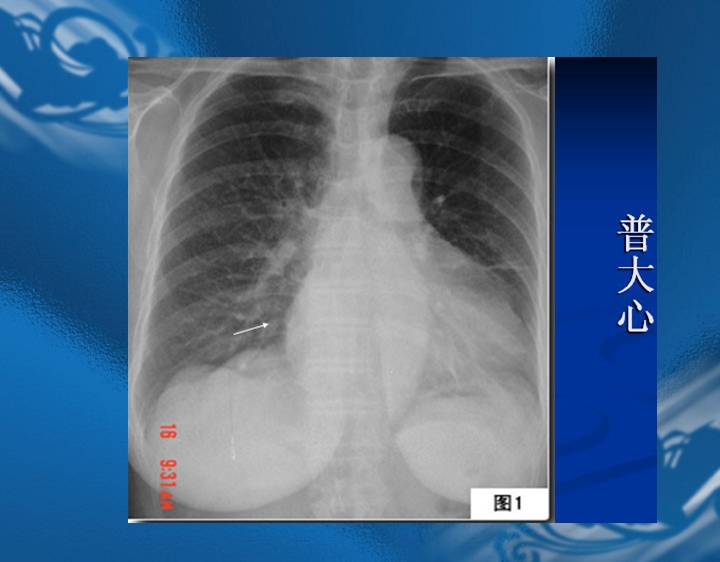

执业医师资格考试“实践技能”影像学辅导资料